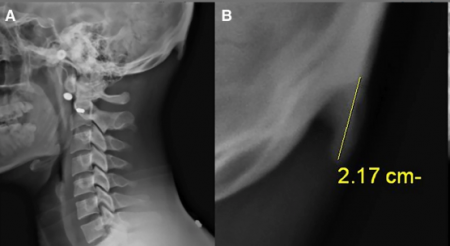

Это явление, получило название "текстовая шея", - это когда шея сильно напрягается, чтобы стабилизировать голову, в то время как голова направлена вниз для просмотра устройств, таких как смартфоны и планшеты. Такое положение головы становится дополнительной нагрузкой для мышц, соединяющих шею с затылком. В ответ на постоянное напряжение мышц, сухожилий и других соединительных тканей на черепе начинают формироваться новые выросты, которые расширяют площадь крепления мышц, обеспечивая им большую плотность и силу.

Исследование проведенное австралийскими учеными из University of the Sunshine Coast, Дэвидом Шахаром в 2016 году, показало, что из 218 обследованных пациентов 41% имеют костный нарост на черепе, связанный с длительным использованием смартфона. Другое исследование, проведённое в 2018 году, где обследовалось уже 1200 пациентов подтвердило эти выводы.

Исследование показало, что нарост чаще встречается у мужчин, чем у женщин, 67% против 20%. Самый длинный нарост в 35,7 мм был у мужчины и 25,5 мм у женщины. Больше всего подвержены этому изменению люди в возрасте от 18 до 30 лет (те кто чаще использует смартфон).